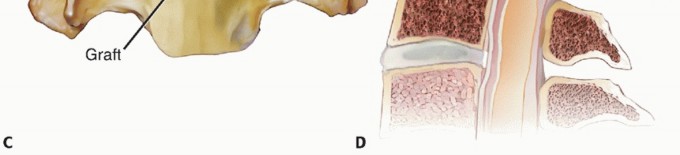

### TECH FIG 1 • A. The discectomy should be performed from uncus to uncus. The upslope of the uncinate is clearly defined with curettes and Kerrison rongeurs until these borders are unquestionably identified. Having a wide discectomy allows for placement of larger grafts or supplemental grafts in the uncinate regions. B. ACDF graft carpentry in a patient with three level cervical spondylotic myelopathy. Creating parallel disc spaces facilitates graft-host bone contact, securing an intimate fit as well as allowing for wide decompression of spurs arising from the posterior disc space. Posterior spurs along the floor of the canal have been removed at each level, decompressing the spinal cord. The central portion of each endplate is maintained as much as possible to optimize structural integrity. At C6-C7, two grafts have been inserted in order to fill the disc space as much as possible (note as a result the different appearance of the grafts at C6-C7 vs. the proximal levels). ### Use of Distraction: Pins, Tongs, and Spreaders Intervertebral body distraction pins can be placed to gently distract the disc space and improve visualization. Generally, this is done after an initial superficial discectomy, which allows greater disc space mobilization with the pins. Because greater preparation of the inferior endplate of the superior vertebra is usually needed, the Caspar pin should be placed more cephalad in the cephalad vertebral body (TECH FIG 2). Overdistraction of the disc space is not desired. If the disc space is fused in an overdistracted position, postoperative neck pain may result. If there is a significant compressive lesion on the spinal cord, distraction should be avoided until the compression has been relieved to prevent stretching or tenting of the cord over that lesion. An additional benefit of the Caspar pins is that they help to retract the soft tissues in a cephalocaudal direction without the use of a secondary set of retractor blades. Alternatively, a small laminar spreader can be used in the contralateral disc space instead of Caspar pins to provide distraction. ### Endplate Preparation The inferior endplate of the cephalad level is concave, whereas the superior endplate of the inferior level tends to be relatively flatter. Thus, to achieve intimate contact of bone graft with both 4 endplates, a rectangular space is created by parallel decortication of the endplates.

### TECH FIG 9 • Measuring the interspace without (A,B) and with (C,D) distraction.

### TECH FIG 10 • The cortical graft in place with (A,B) and without (C,D) distraction. Without distraction, the graft is compressed by the natural elasticity of the cervical spine. There is about 2 to 6 mm of free space between the posterior surface of the graft and the spinal cord.